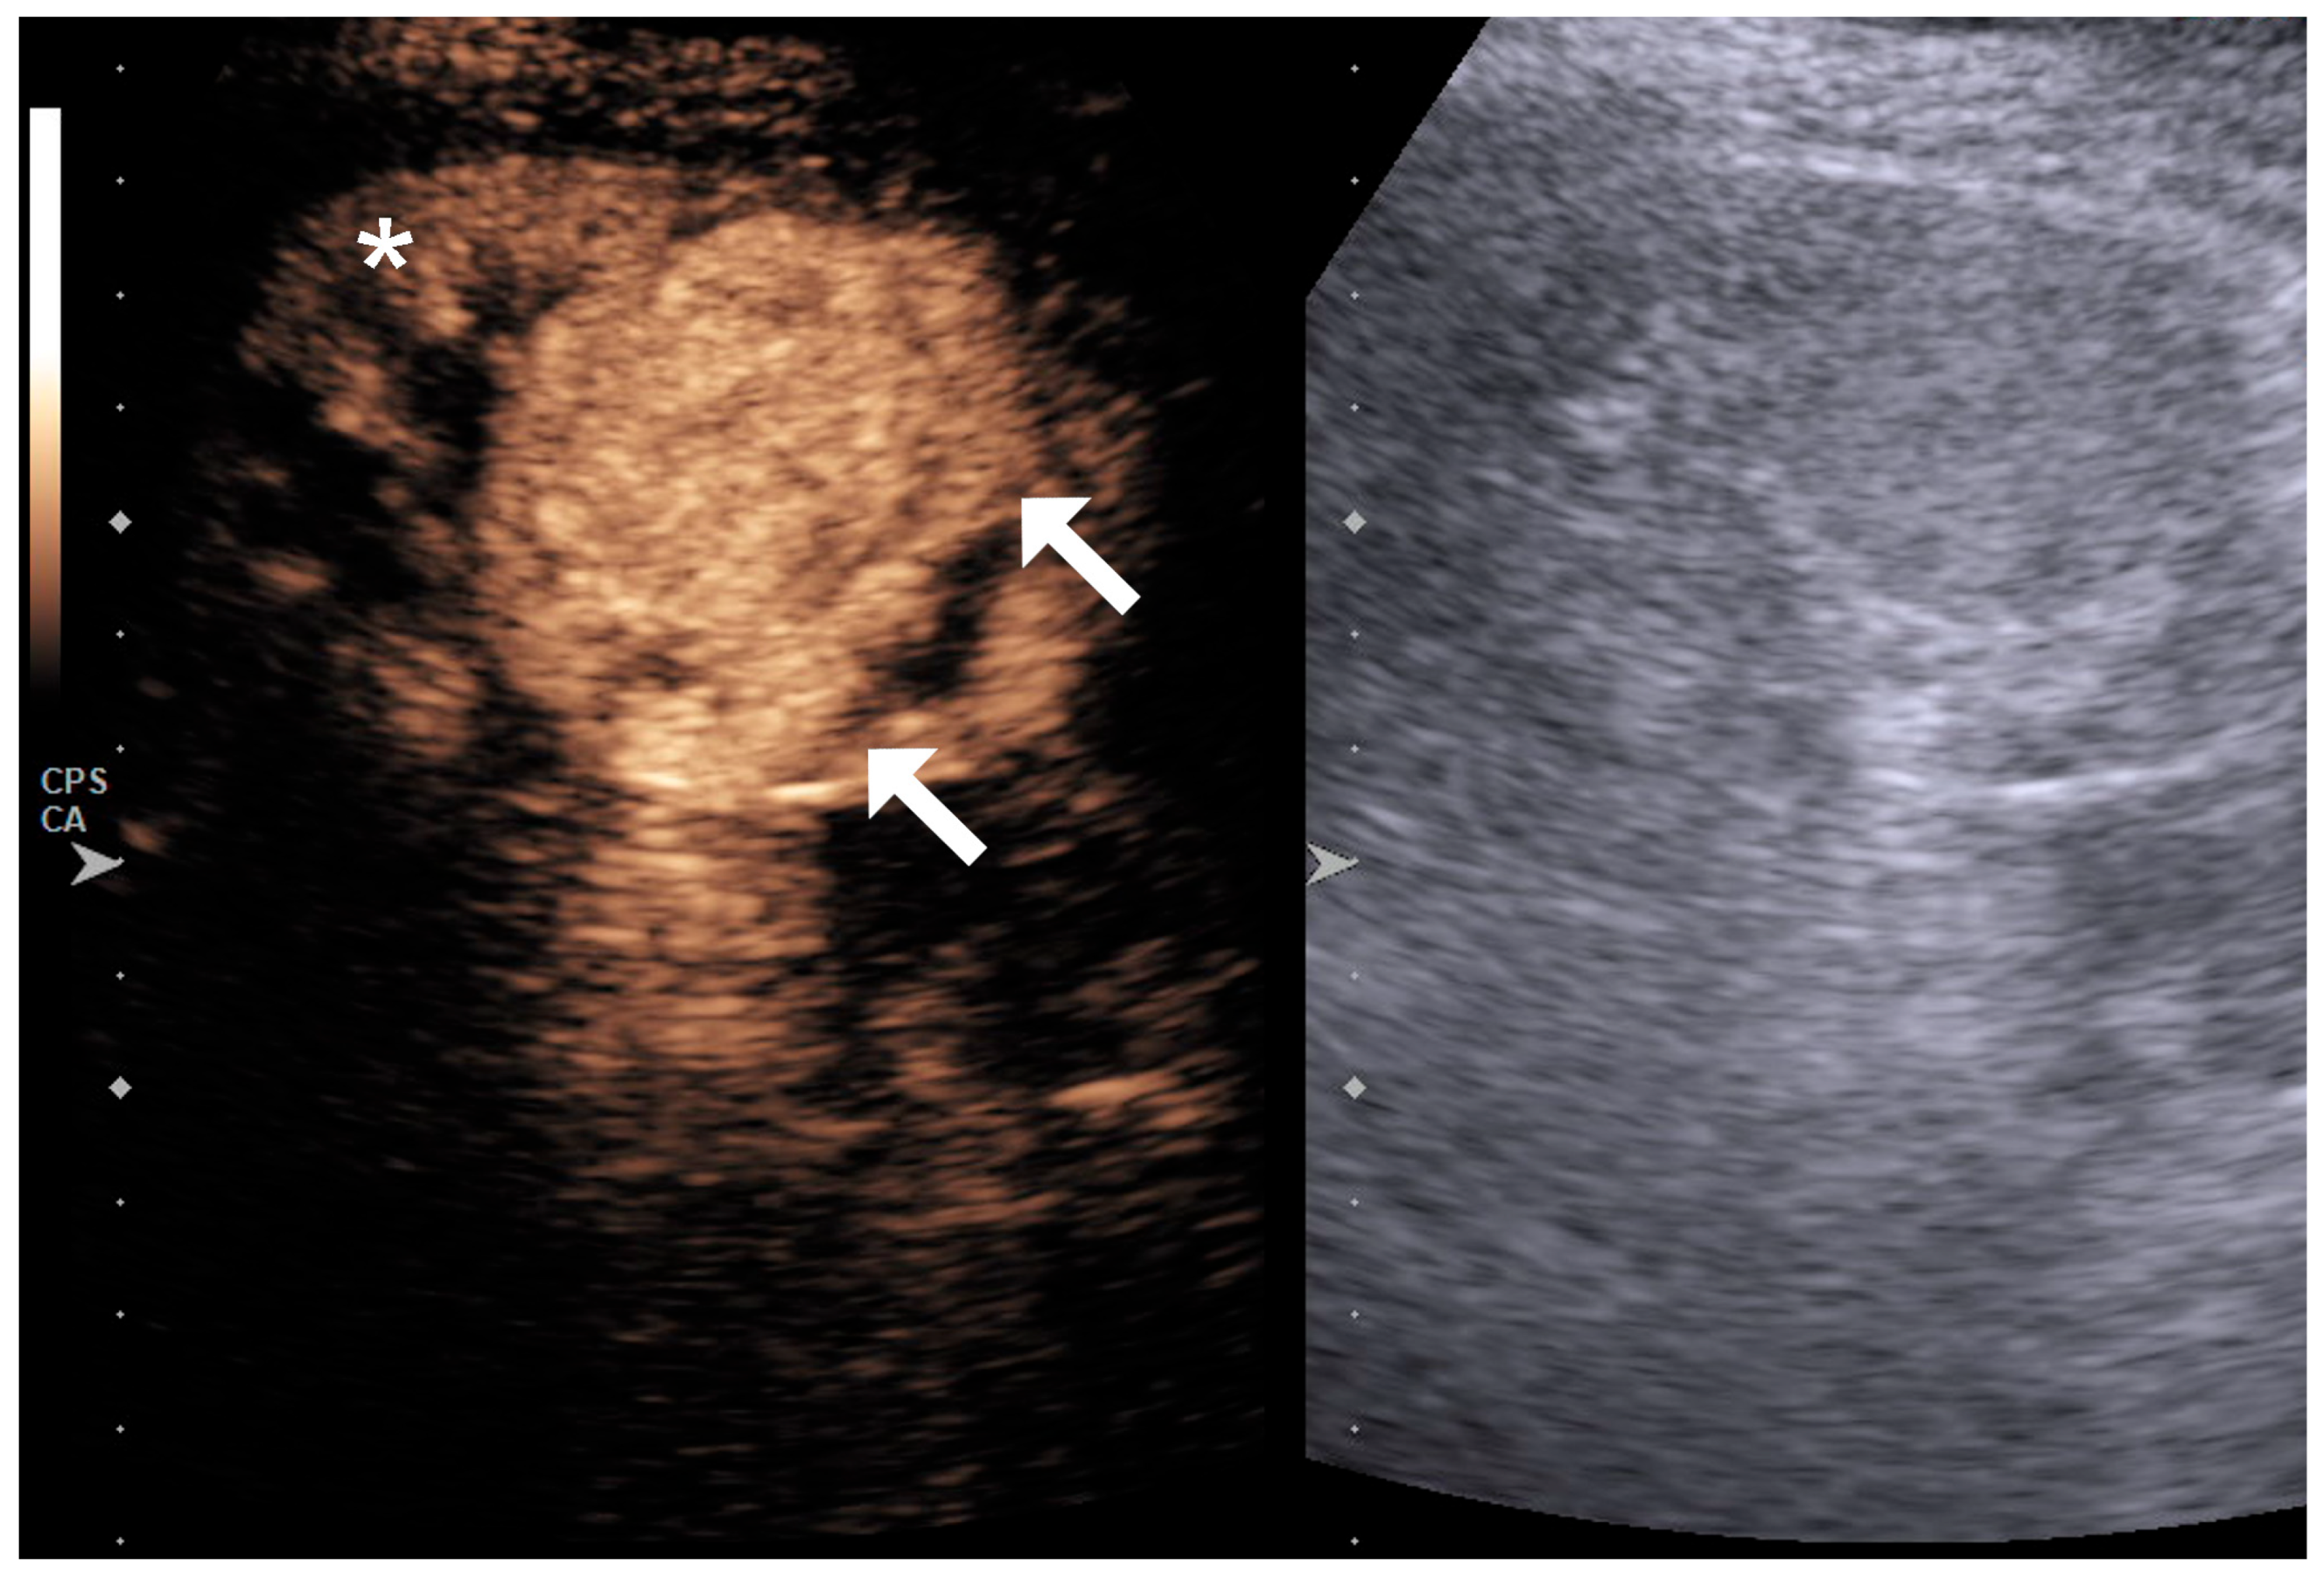

4.1. Qualitative Evaluation